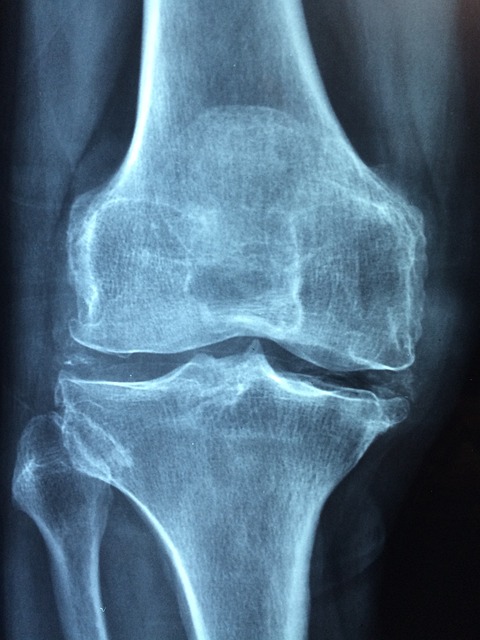

무릎에 물이 찼다는 것은 의학적으로 관절강 내에 관절액이 과도하게 고여 있는 상태를 말합니다. 주로 무릎 연골 손상, 관절염, 혹은 외상으로 인해 발생합니다.

이 상태에서 러닝을 하면 무릎 관절에 압력이 더해져 상태가 악화될 수 있습니다. 따라서 단순한 피로 통증과 달리 반드시 상태를 구분할 필요가 있습니다.